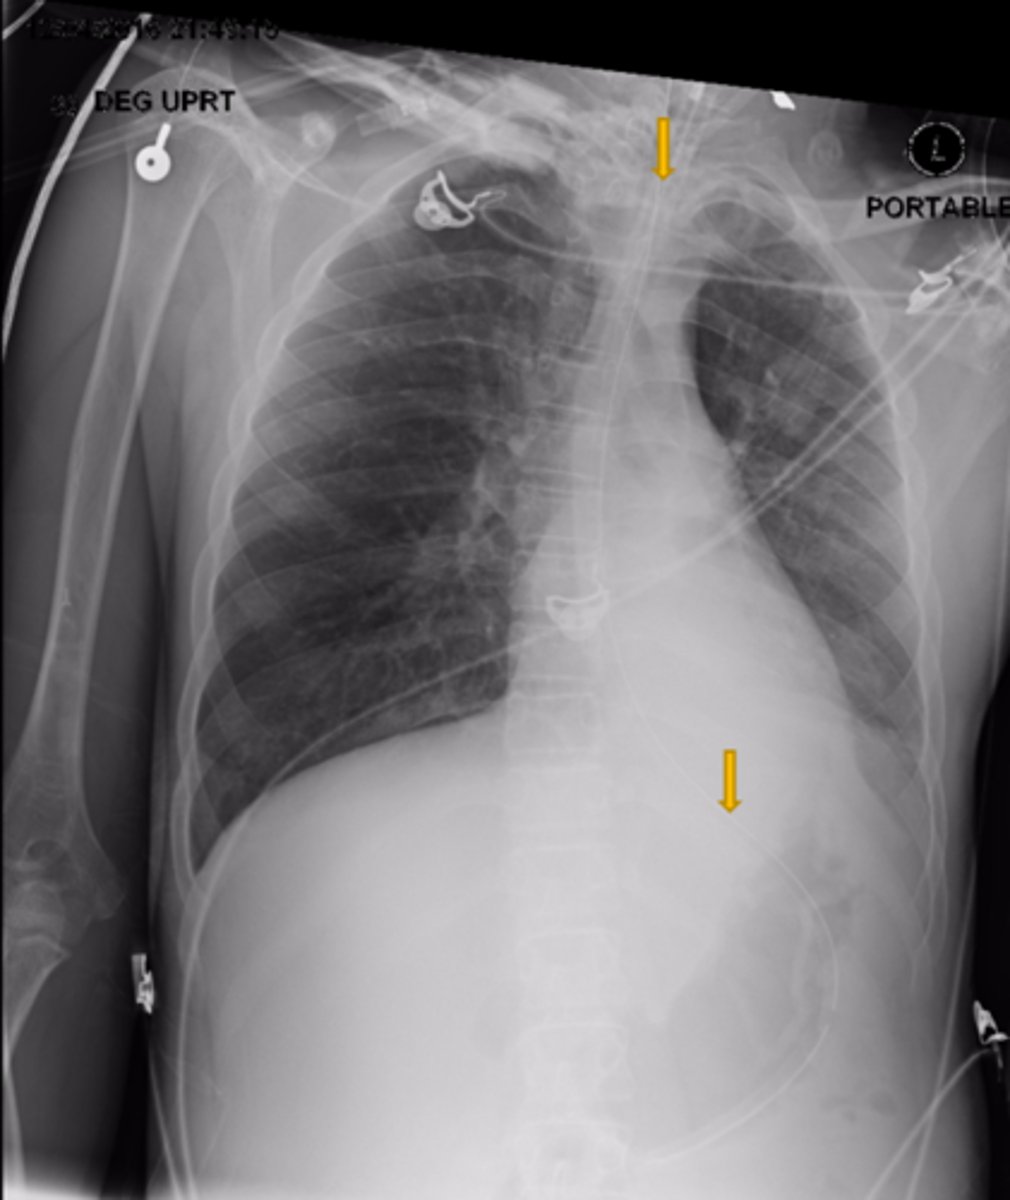

Is this patient rotated?

Yes

Is the Cardiac/Thoracic ratio normal?

Possible CHF (presence of Kerley B lines)

What does the chest film show?

NG OG

What is the structure the yellow arrows are pointing at?

No

Is this a high-quality film?